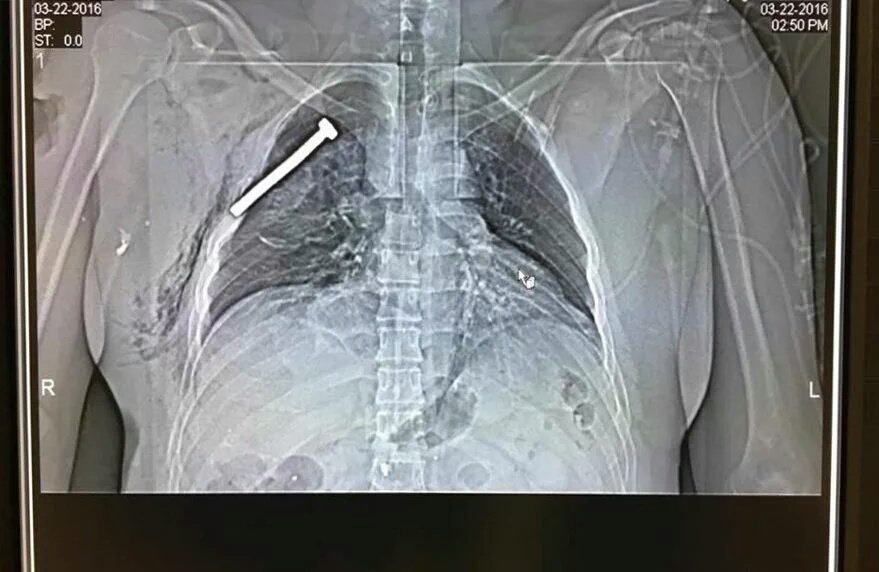

Про состояние нашей "скорой помощи" я делал репортаж в прошлом году . Некоторые читатели тогда сетовали, что в связи с большими расстояниями в Новой Москве, на прибытие медиков может быть потрачено много времени, а ведь существует такое понятие как "золотой час", когда шансы спасти больно ...